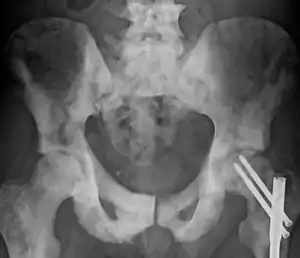

Several tests can be used to look for evidence of spread. Medical specialty professional organizations, including the American Urological Association and European Association of Urology, recommend against the use of PET scans, CT scans, or bone scans when a physician stages early prostate cancer with low risk for metastasis.[110][111][112][113][114] Those tests would be appropriate in cases such as when a CT scan evaluates spread within the pelvis, a bone scan looks for spread to the bones, and endorectal coil magnetic resonance imaging evaluates the prostatic capsule and the seminal vesicles. Bone scans should reveal osteoblastic appearance due to increased bone density in the areas of bone metastasis—the reverse of what is found in many other metastatic cancers.[115]

Extent of cancer spread for purposes of staging is best assessed by MRI. CT scans may also be used, but are less able to detect spread outside the prostate than MRI. Bone scintigraphy is used to test for spread of cancer to bones, though bone areas that take up the radiopharmaceutical can instead be due to other conditions that affect bone health.[116]